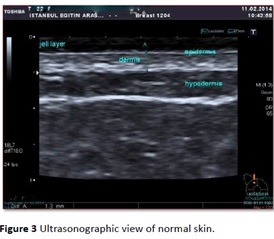

? ? ? ? 使用18MHz頻率的通用超聲掃描正常皮膚,傾斜的箭頭顯示真皮的界限,真皮的兩層(淺層和深層的回聲)。

? ? ? ? 第二幅圖是日本某品牌3-18 MHz超聲掃描的皮膚圖像。D. Karacetin等“乳腺癌患者放療所致皮膚毒性的的高分辨率超聲評價”。發表在癌癥研究雜志,2016卷第4期 ,可見圖像質量比其它品牌超聲要好得多,但與真正的超聲皮膚影像和組織學仍相去甚遠。

? ? TPM DUB系統15-18 MHz掃描的皮膚圖像,清晰地顯示和測量皮膚全層的影像。Gel-耦合劑,EP-表皮,DER-真皮,HYP-脂肪,FAS-淺筋膜,MSC-肌肉